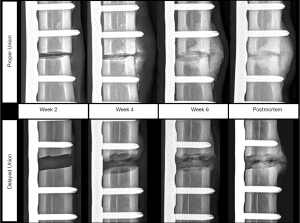

For the DU fracture model, all animals exhibited maximum midspan antenna sensitivity within the first two weeks post-surgery (mean 8.75±3.50 days post-surgery), and tended to decrease until animal sacrifice (Figure 8). For all DU specimens, the normalized midspan antenna sensitivities remained below 50% after four weeks post-surgery. Normalized midspan antenna sensitivity for this group decreased by an average of 81.2%±18.0% from maximum sensitivity to sensitivity at study’s conclusion. The first radiographic indications of fracture site mineralization for the DU specimen occurred between weeks four and eight (Figure 9). Each specimen exhibited visual radiopacity at the fracture site, but had yet to achieve full cortical bridging; thus, it was concluded that all animals in this group exhibited a delayed fracture union healing pathway. The animals in the PU fracture model exhibited maximum midspan antenna sensitivity at 19.00±11.58 days. Initial radiographic indications of fracture site mineralization occurred between three and four weeks post-surgery (Figure 9). All specimen in this group achieved clinical union based on successful cortical bridging at the animals’ sacrifice.

The biomechanical, histology, and µCT data suggest the two cohorts of this study to be a reasonable approximation of normal and aberrant/delayed fracture healing. In vivo radiographic evidence of callus mineralization was temporally adequate in the PU group (i.e., callus radiopacity appearing three to four weeks post-fracture) but was considerably postponed for the DU group (i.e., callus radiopacity appearing four to eight weeks post-fracture); thus, this study partially recapitulated the diagnostic deficits of X-ray imaging for predicting fracture healing outcome. This is further supported by the appearance of radiopaque tissues at the fracture site in three of four DU animals despite reduced fracture stiffness (Figure 7B). These findings are consistent with current literature where it has been established that planar radiographic images are a poor predictor of stiffness (26) and strength (60) of the healing fracture.